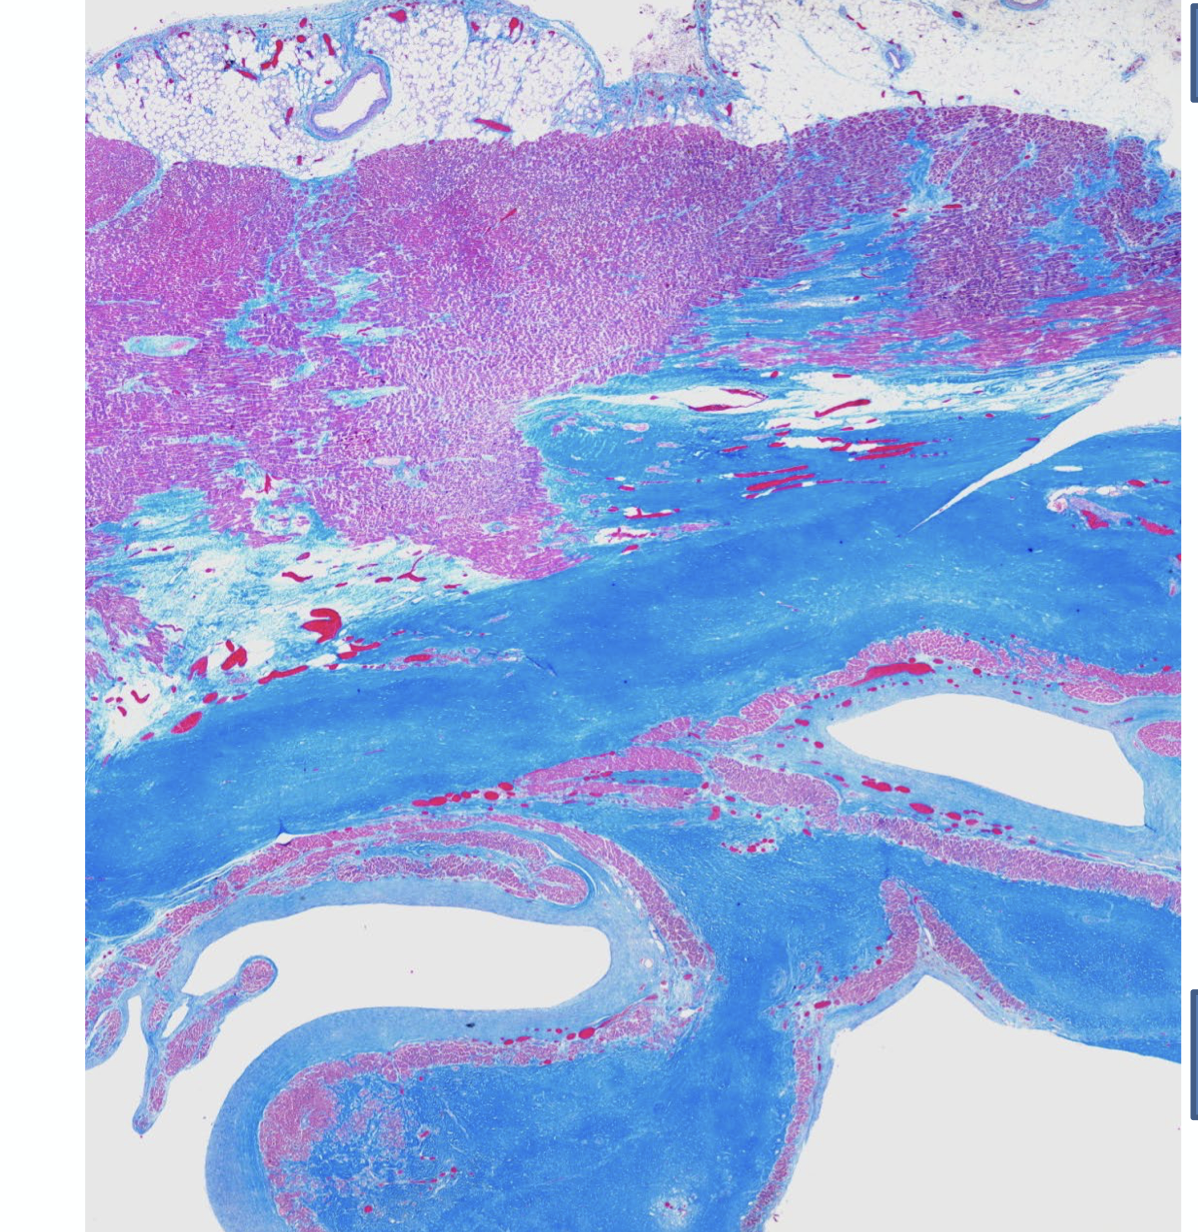

myocardium gets stained blue, which indicates a ___ infarct

a remote infarct. Fibrosis happens after a few days-weeks, the infarct happened a little while ago.